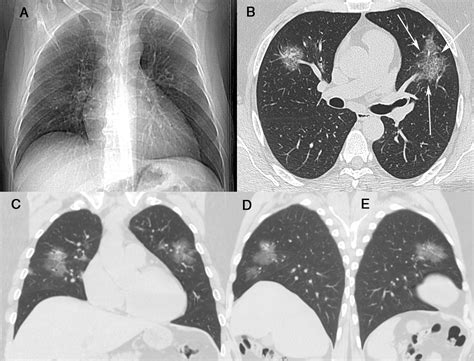

• Multifocal GGO: Appearing in several different areas across one or both lungs.

• Diffuse GGO: Spreading widely throughout the lungs, which often points to a systemic process.

• Infections: Viral pneumonia (including COVID-19), bacterial infections, or fungal infections often present as GGOs.

• Inflammation: Conditions like hypersensitivity pneumonitis or sarcoidosis can cause widespread inflammatory changes.